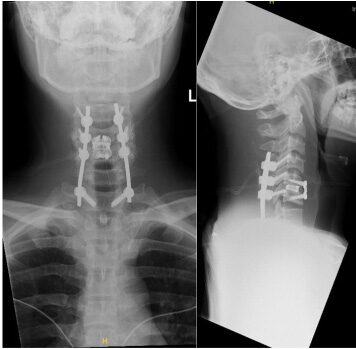

Posterior fusion and laminectomy with ACDF

X-rays of a patient treated with anterior cervical diskectomy and fusion (ACDF)